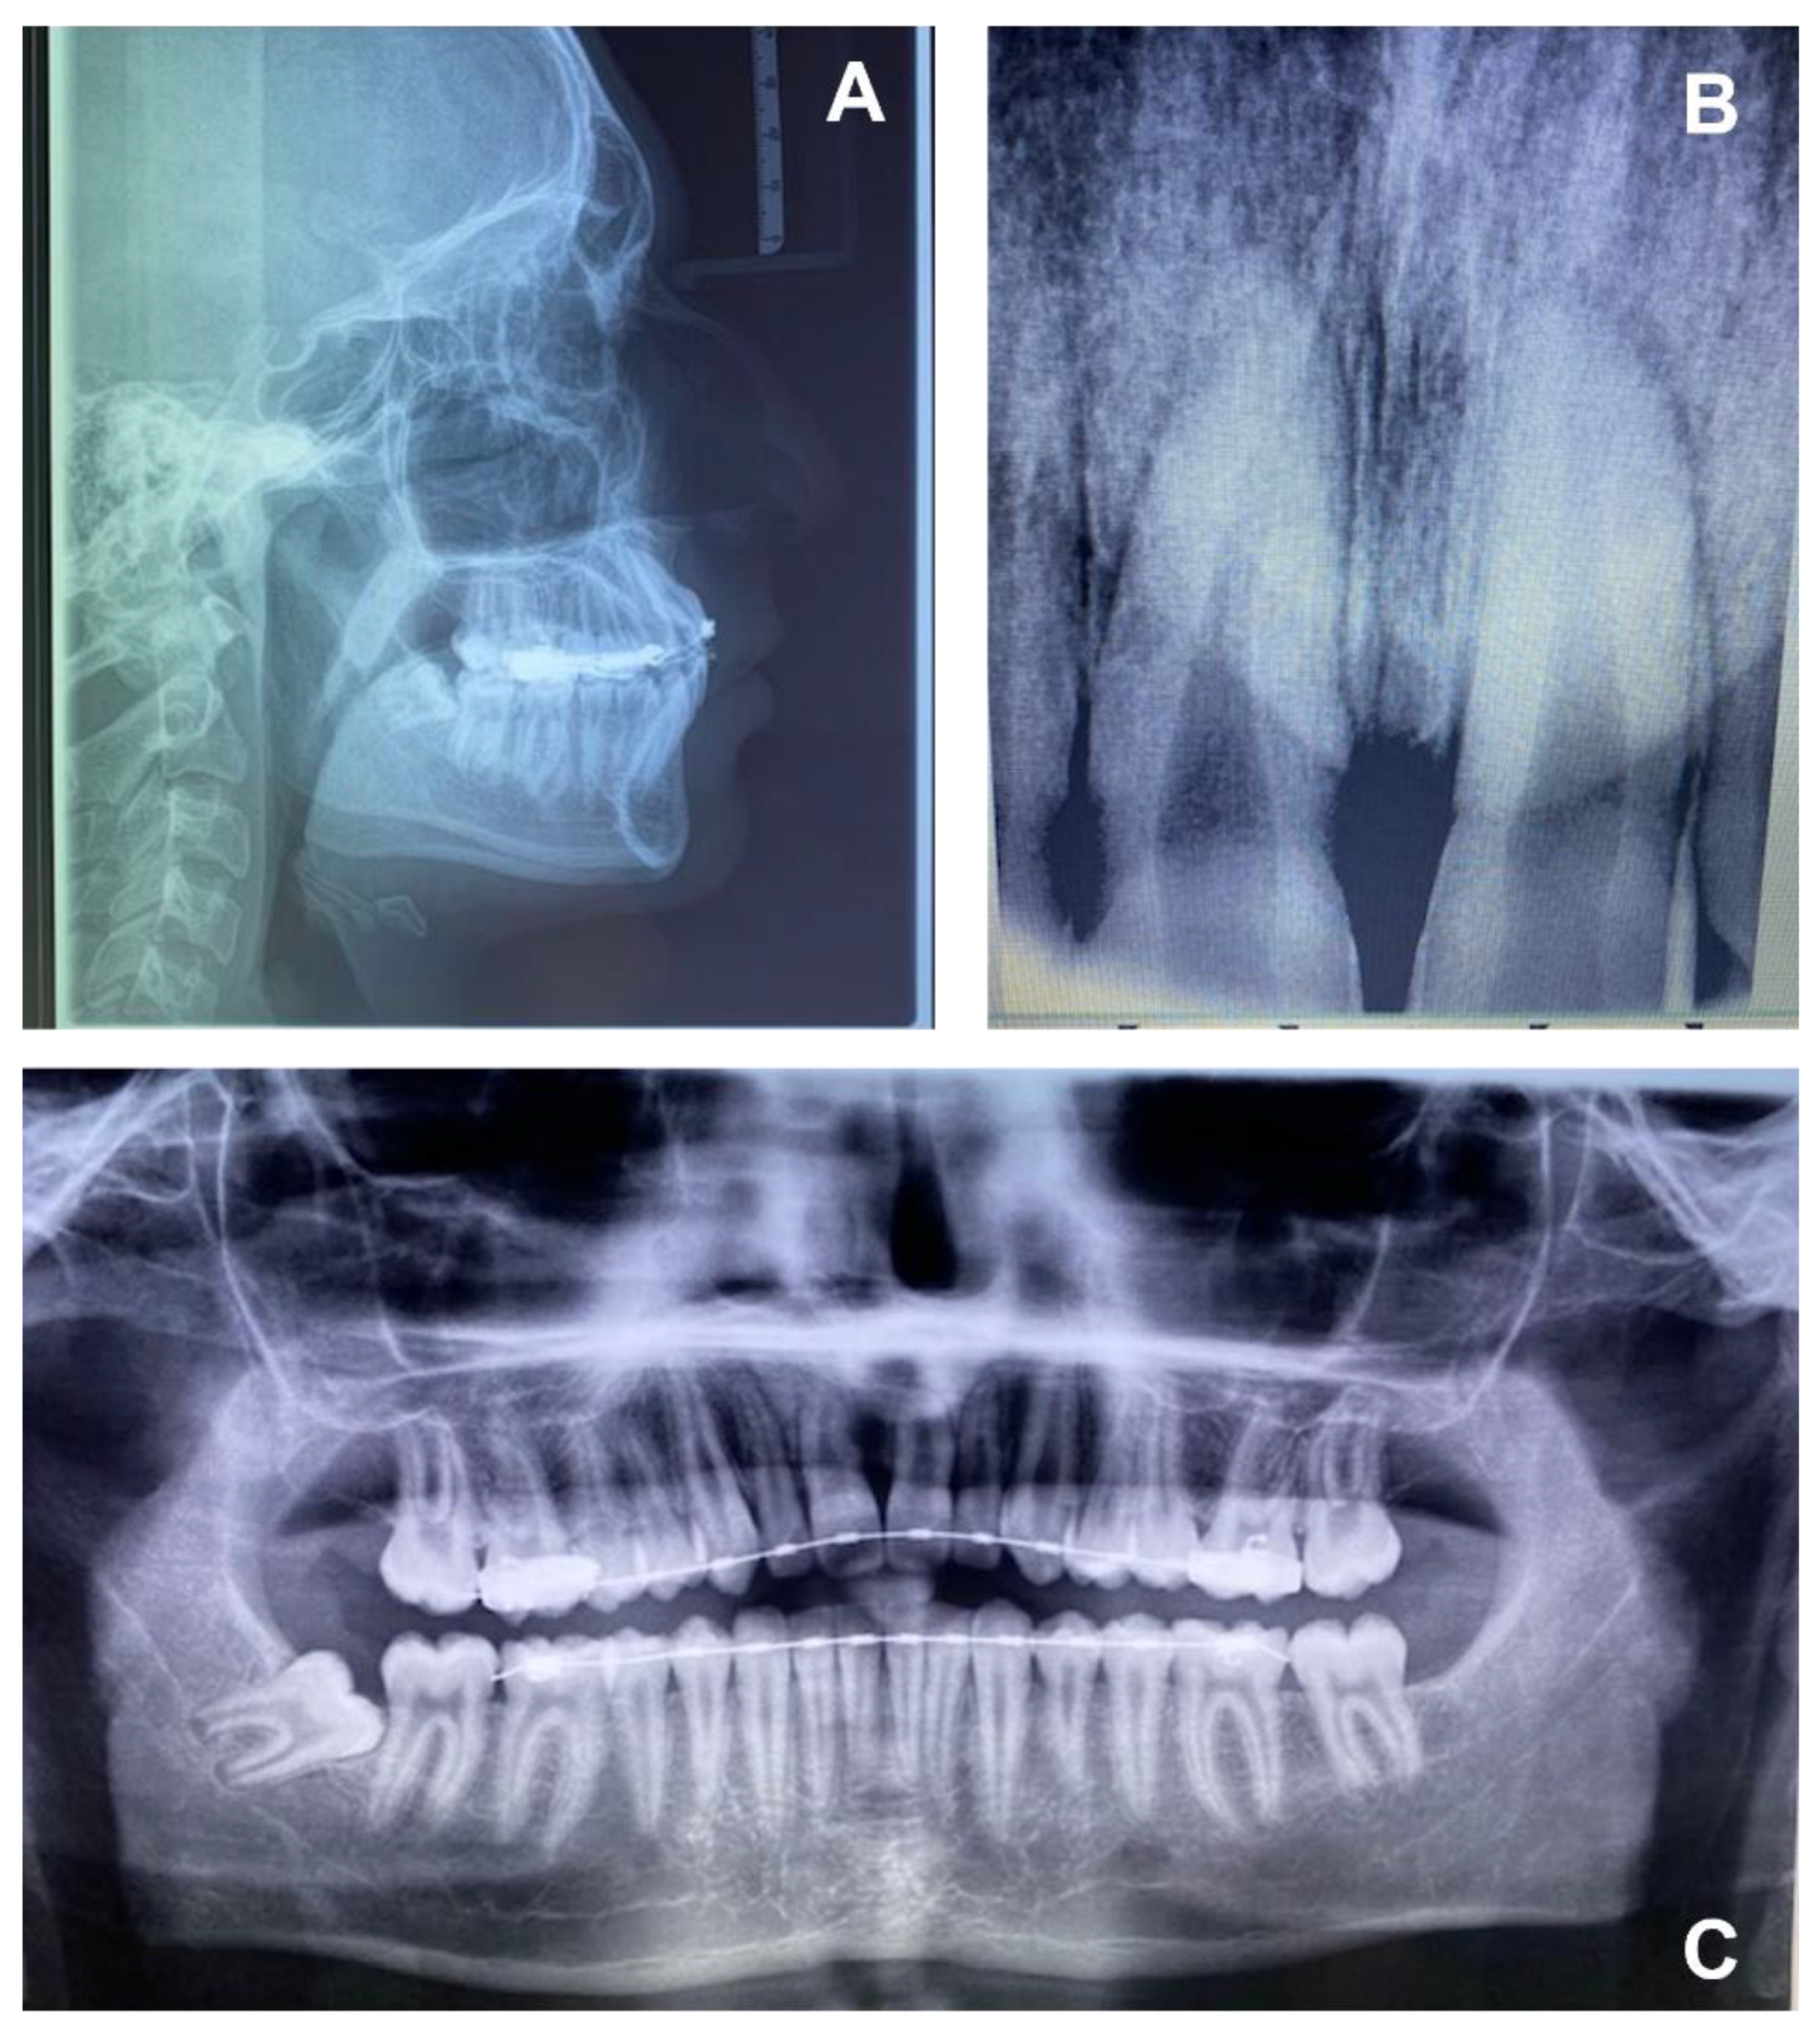

- Intraoral X-rays with periapical and occlusal projections confirm the presence, position and/or anomaly of the retained maxillary incisors and any underlying developmental anomaly or pathology. The buccolingual position of the non-erupted tooth can be localized using horizontal or vertical parallax.

- Ortopanthomography X-ray (OPG X-ray) to evaluate the problem in relation to the entire arch, adjacent tooth and the staging of the eruption of the other dental elements.

- Latero-Lateral Teleradiography (LLT) of the head with cephalometric trace to assess the height and inclination of the crown and root of the impacted tooth.

2.2. Clinical Exams and Diagnosis

| Values | Normal | |

|---|---|---|

| SNA | 80.4° | 82°+/−2° |

| SNB | 78.8° | 80°+/−2° |

| ANB | 1.6° | 2°+/−2° |

| GONIAC ANGLE | 116.1° | 130°+/−7° |

| INTERINCISIVE ANGLE | 98.4° | 131°+/−6° |

| SUPERIOR INCISOR ANGLE | 51.2° | 22°+/−2° |

| INFERIOR INCISOR ANGLE | 28.9° | 25°+/−2° |